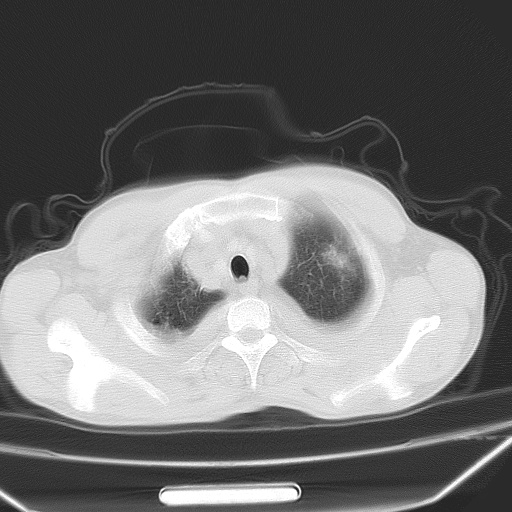

双肺野对称性磨玻璃影,分布于内中带,双侧胸水,患者有咯血。

双肺野广泛对称性磨玻璃影、实变影,以肺门为中心,主要分布于内中带,符合典型肺泡性肺水肿;伴双侧胸腔少量游离积液。结合患者既往病史且咯血就诊,支持多因素(尿毒症等)所致之肺水肿、肺出血、胸水;影像表现暂不考虑心源性水肿,且症状也不太符。需密切随诊结合临床治疗等进一步明确。

心影增大密度略低,双肺磨玻璃样高密度影及双侧胸腔积液,考虑心功能不全继发双肺肺水肿及双侧胸腔积液。心影密度略低,考虑贫血所致。